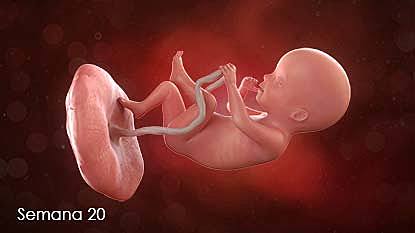

Desarrollo del feto en la semana 20: Ya están formados los órganos vitales

¡Estás en la semana 20, ya están en la mitad del embarazo! Aquella diminuta célula hoy, 18 semanas más tarde, ya mide unos 20 centímetros y pesa casi un cuarto de kilo. En las próximas 20 semanas, el bebé dará "un estirón" espectacular: duplicará su longitud y multiplicará por diez su peso.